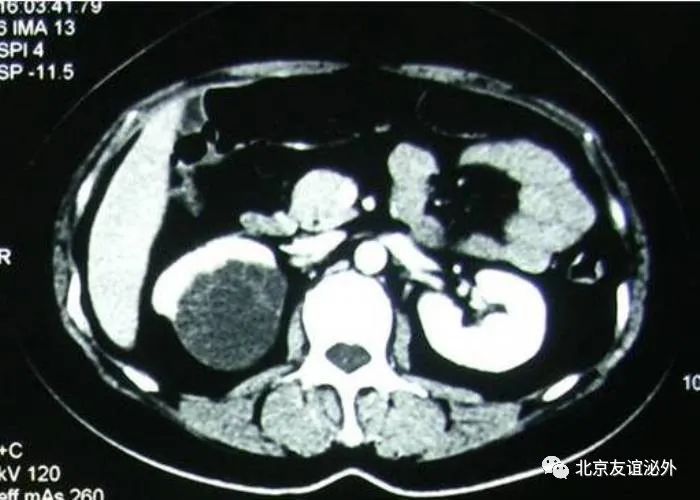

图3. Bosniak II级良性囊肿(囊肿内少量细小分隔)